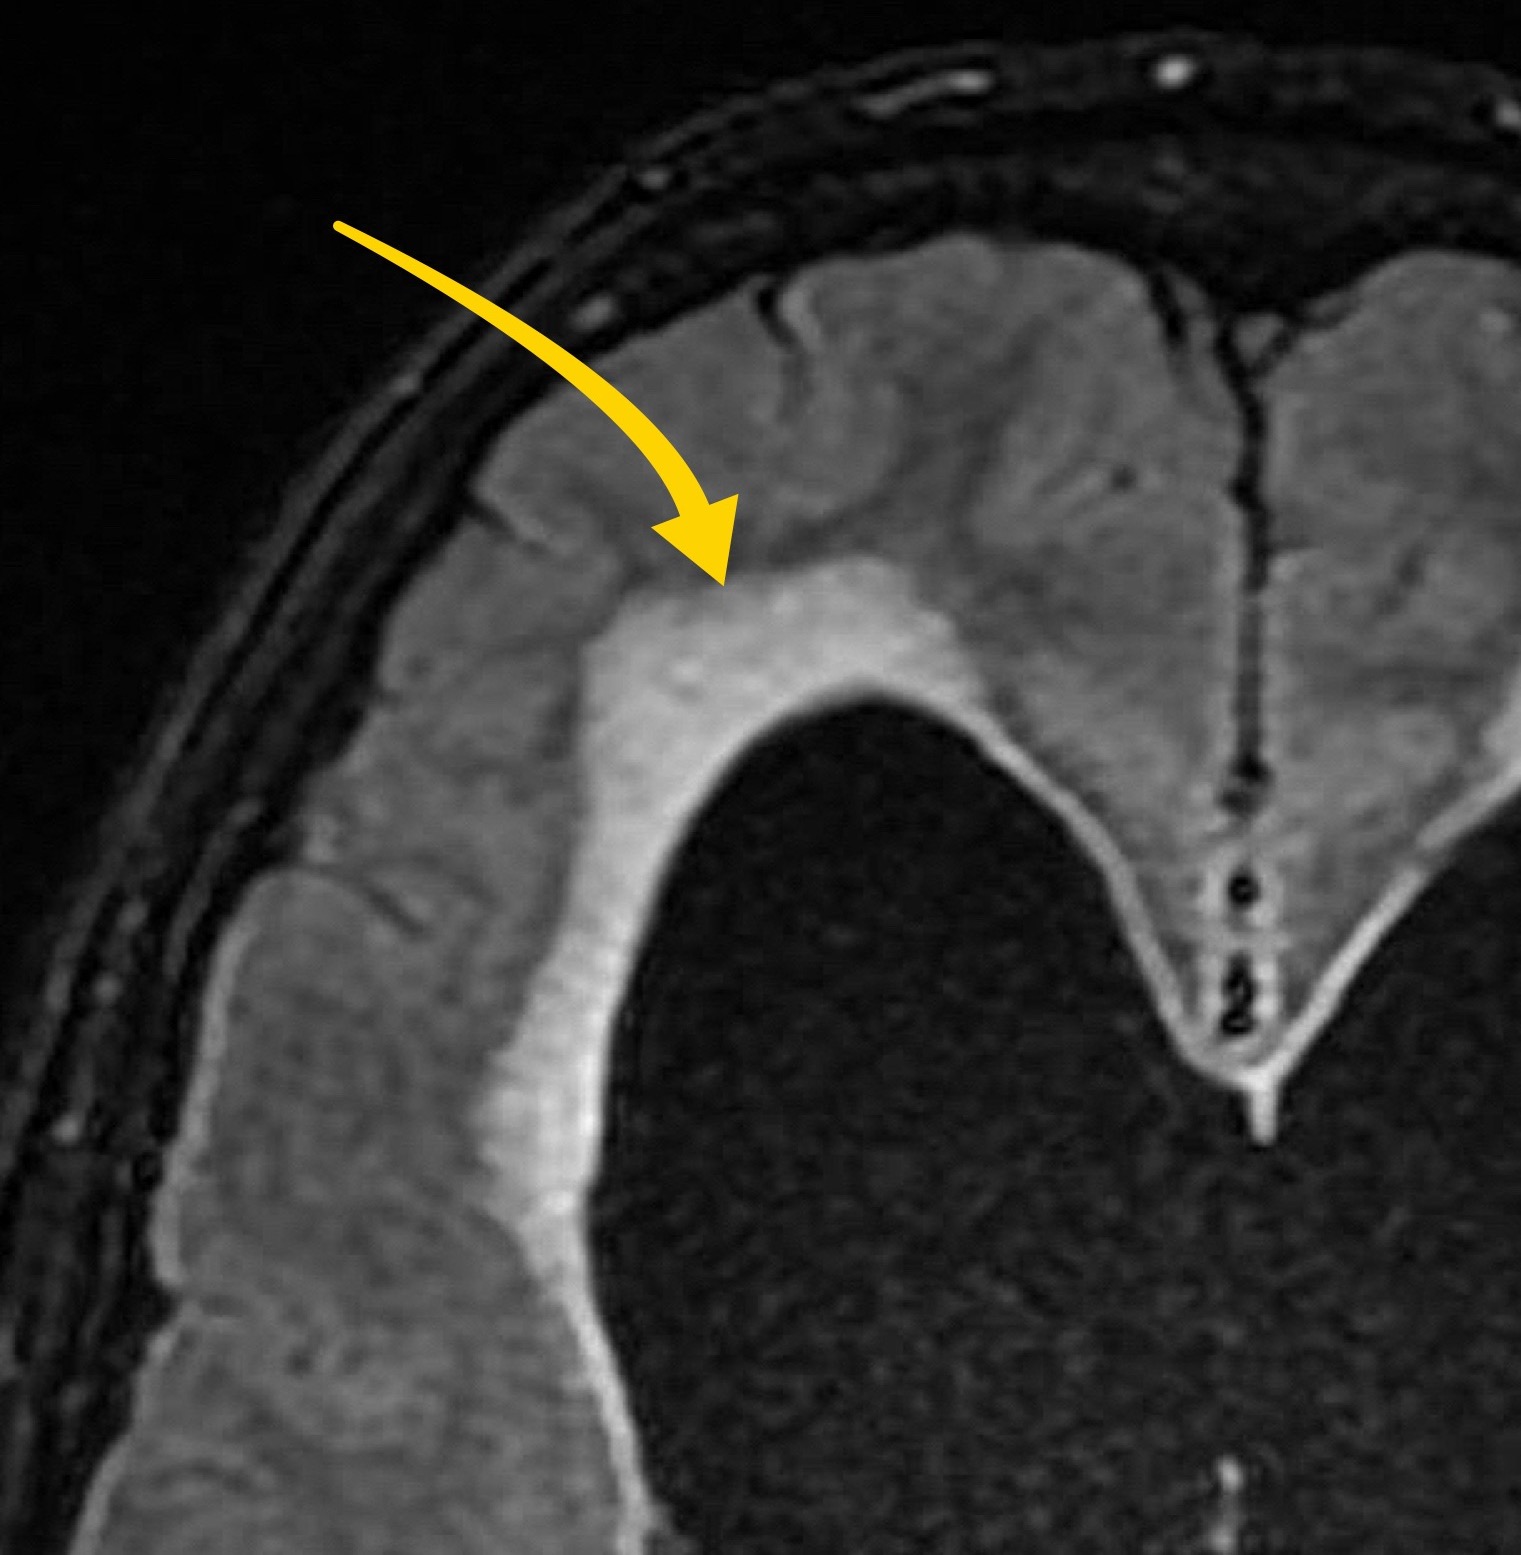

Case 2

A male in his 70s presents with right sided weakness. Have a look at this image from a non contrast CT head. What best describes the finding and most likely diagnosis?

Choose from one of the following options: